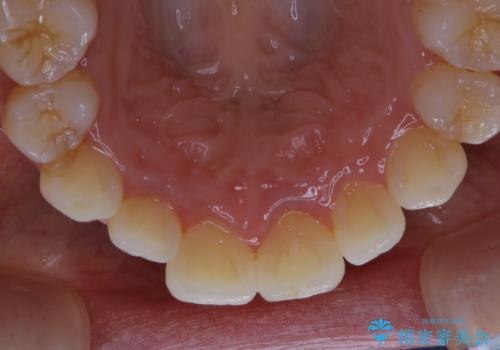

久々の来院で歯のクリーニング PMTC60分コース

- しばらく来院できなかったため、全体的にチェックとクリーニング希望でした。PMTC60分コースを行いました。

歯にステイン(着色)や歯石などが付着していると、汚れなのか虫歯なのかの判別が分かりにくく、正確な診断ができないことがあります。

そのため、定期的に専門的な機械や材料を使用したクリーニング(PMTC)をすることで、ご自身本来の歯の状態となります。より、健康なお口の維持をするためには、痛みや症状などが無くてもPMTCを行いお口の中の環境を綺麗にすることがおすすめです。